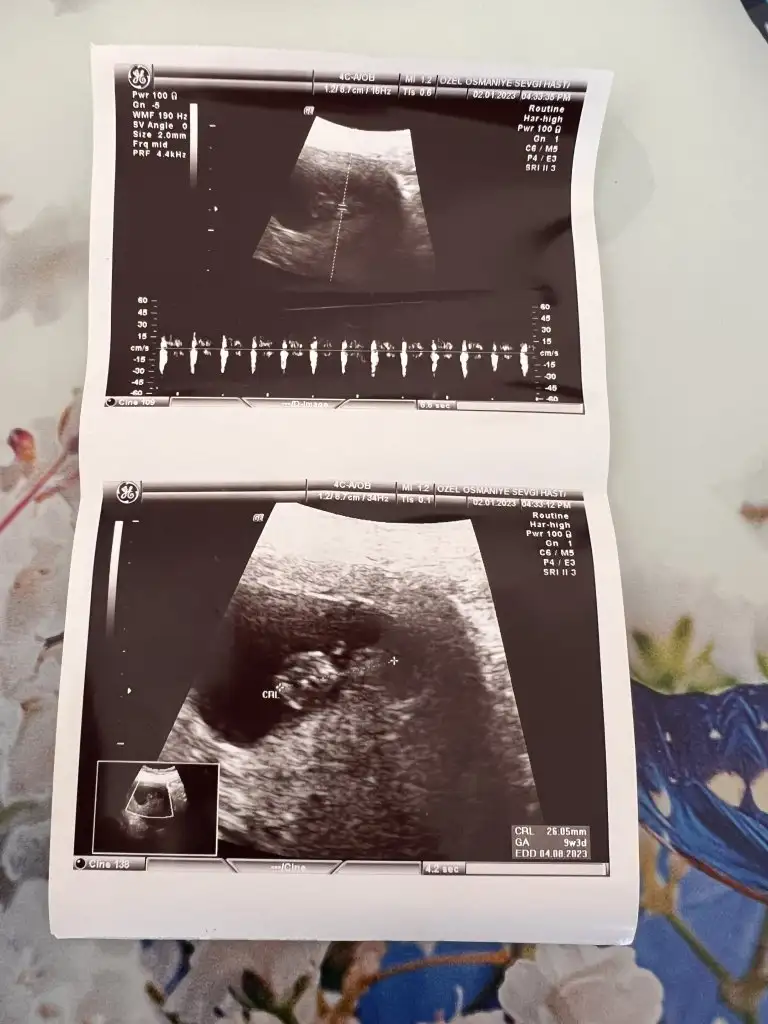

Merhaba banada bakarmısınız

Eşimin doğum tarihi 16.01.1996

Benim doğum tarihi 14.01.2000

Hamile kaldığım ay temmuz ayı son adet tarihimi hatırlamıyorum ama muhtemelen 15 temmuz

8+1 göre minik kızlar hızlı gelişmiyor erkekler hızlı gelişiyor yani buda tutma olasılıgı var ama ben 11 yada 12 hafta nub tahmini ediyorum 😊